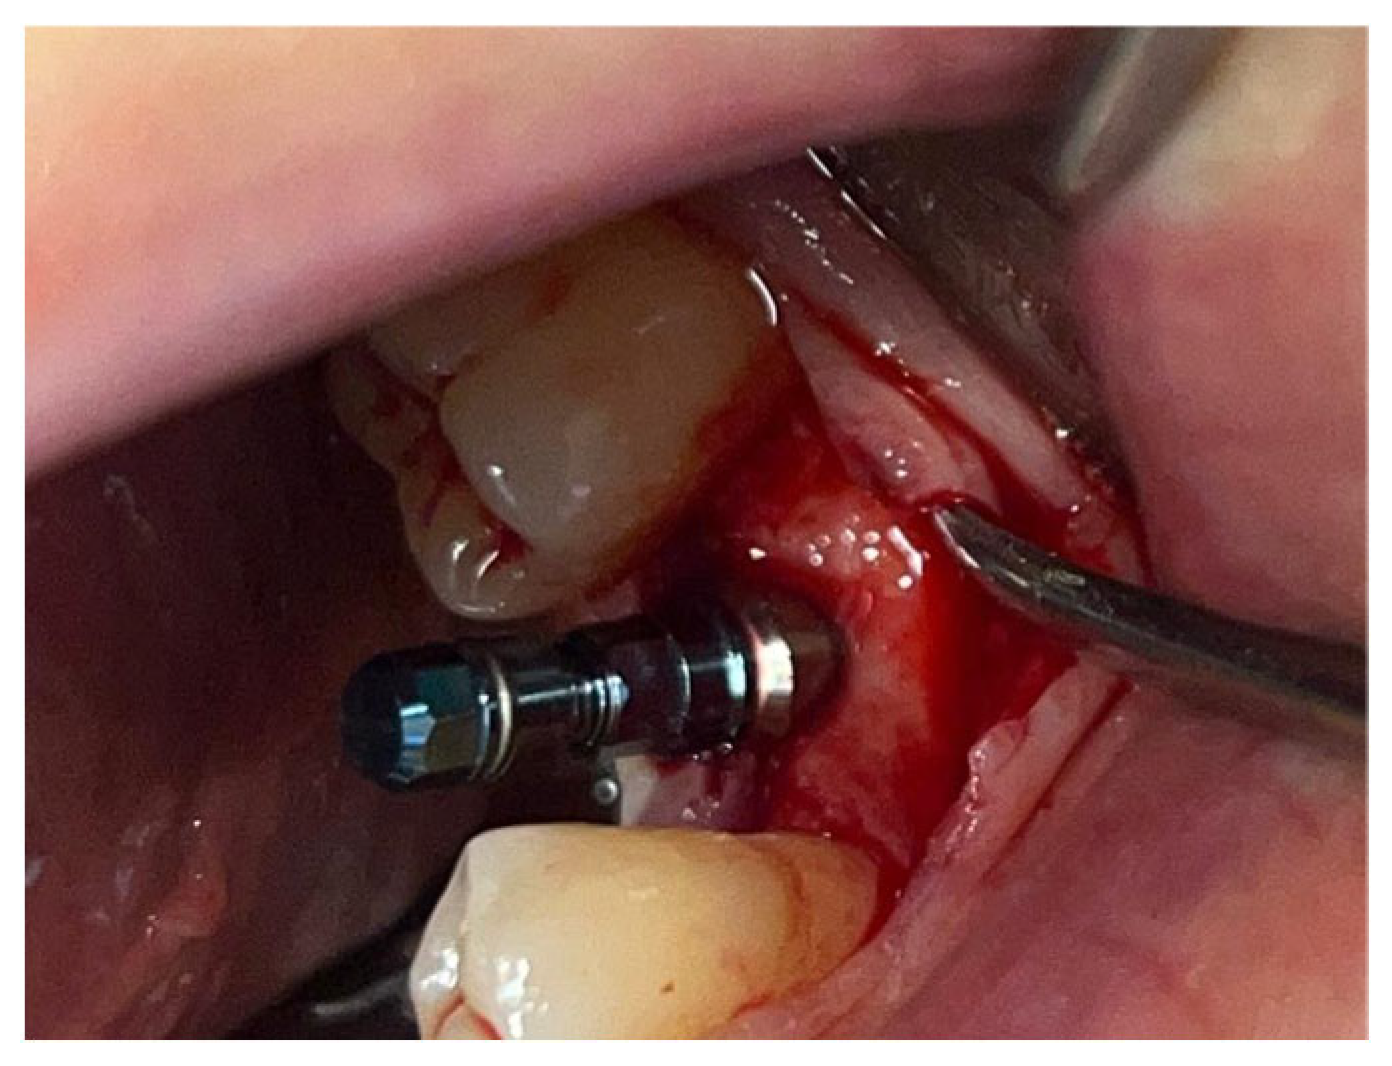

A similar technique was used in a 45-year-old patient with controlled hypertension, treated for the extraction of tooth 1.6 (Figure 11) and subsequent post-extraction implant-prosthetic rehabilitation (Figure 12). The surgical site was treated with bone graft material (Bio-Oss®—Geistlich), and a small amount of Glubran II was applied (Figure 13). Once again, Glubran II proved to be highly effective in stabilizing the graft material at the surgical site, providing excellent hemostasis and strong mechanical resistance from the film formed after polymerization (Figure 14).

Figure 13. Stabilization of synthetic bone material at the surgical site, undergoing implant-prosthetic rehabilitation with Glubran II using an endodontic needle.